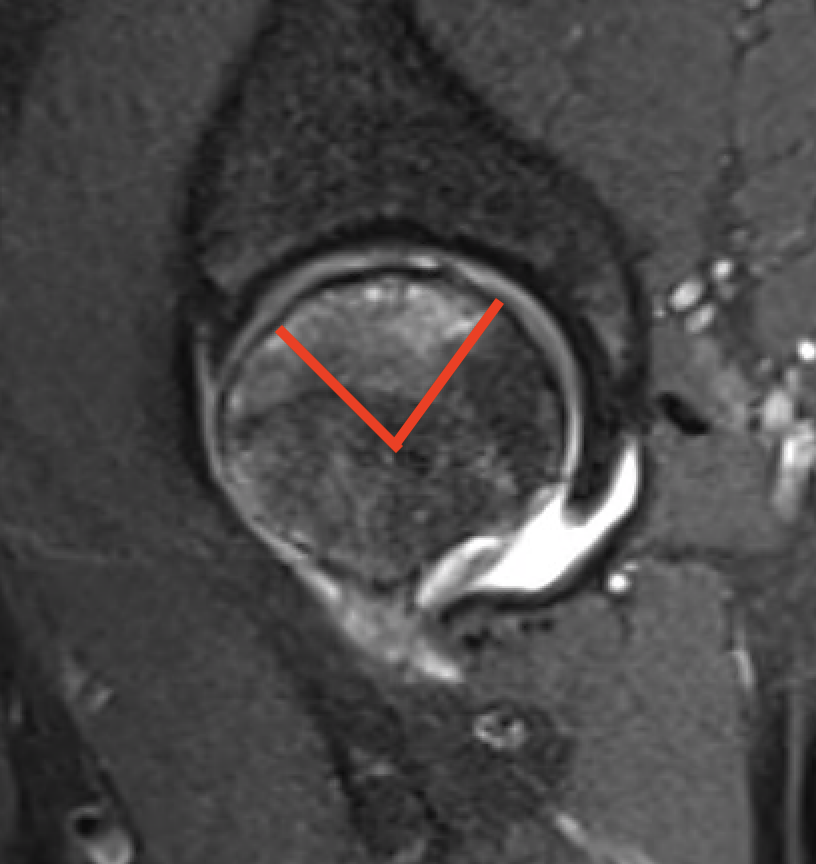

Modified Kerboul Combined Necrotic Angle (CNA)

Adding the arc of the femoral head necrosis

- mid-sagittal and mid-coronal MRI

- low risk collapse: < 190 degrees

- moderate risk collapse: 190 - 240 degrees

- high risk collapse: > 240 degrees

Kerboul CNA

- CNA > 240: 100% collapse

- CNA 190 - 240: 50% collapse

- CNA < 190: 0% collapse